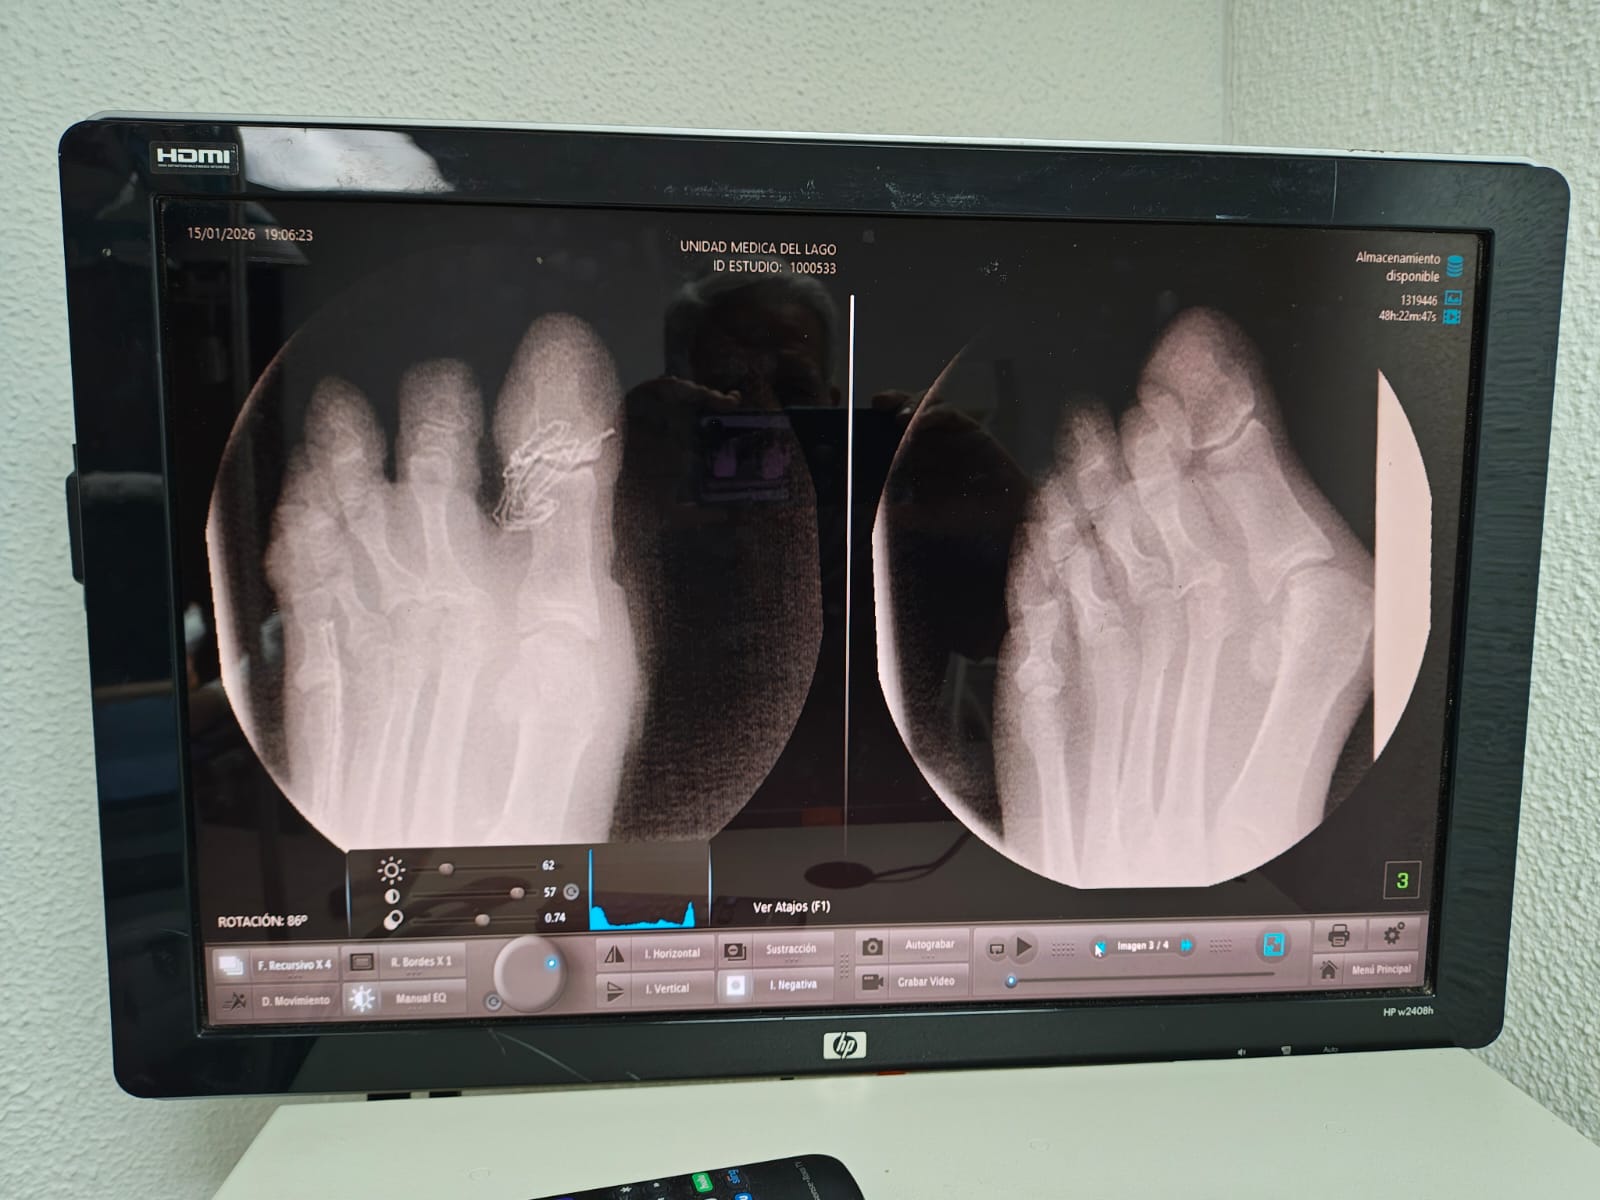

CIRUGIA CON MICRO DRILLS PARA CORRECCION DE JUANETES 18 MIL PESOS